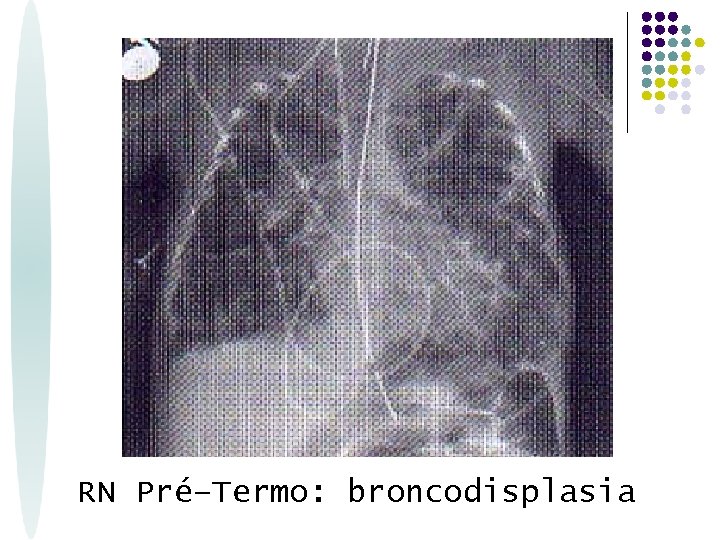

RN Pré–Termo: broncodisplasia